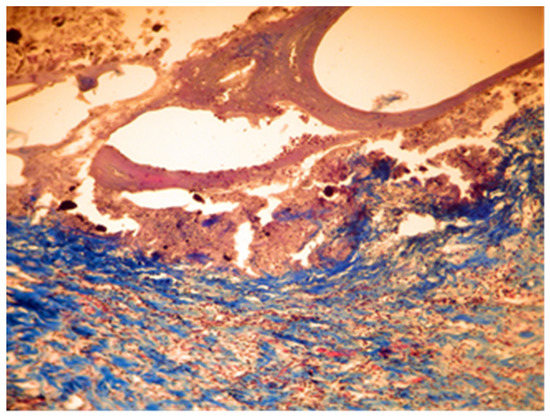

In group C, it was noticed that the local inflammatory reaction induced by the implantation of DiaRoot BioAggregate was much less intense than in groups A and B. The area of necrosis was a small band surrounding the implanted material, with fewer neutrophils and macrophages. Fibroblast differentiation was also reduced (Figure 9 and Figure 10).

Figure 9. Group C. Moderate necrosis area with pieces of implanted material and moderate leukocyte influx. Partial resorption of the implant material. Subcutaneous tissue—7 days after implant. Col. Trichrome Masson, ×100.

Applsci 11 06519 g009

Figure 10. Group C. Moderate necrosis area with pieces of implanted material and moderate leukocyte influx. Partial resorption of the implanted material. Subcutaneous tissue—7 days after implant. Col. Trichrome Masson, ×400.